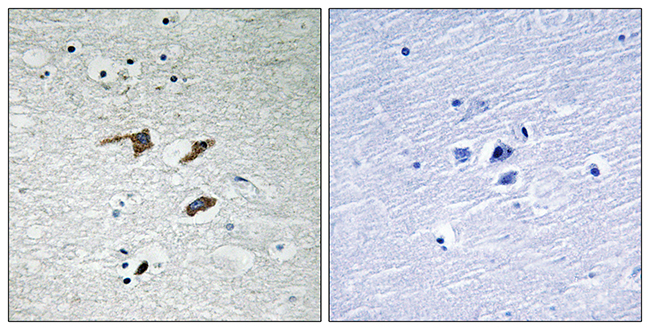

Anti-NPY AntibodyA98310

ApplicationsELISA, ImmunoHistoChemistry

ReactivityHuman, Mouse, Rat